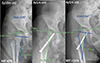

This review brings together a multidisciplinary, multinational team of experts to discuss the current state of knowledge in the detection and treatment of hip displacement in cerebral palsy (CP), a global public health problem with a high disease burden. Though common themes are pervasive, different views are also represented, reflecting the confluence of traditional thinking regarding the aetiology and treatment of hip displacement in CP with emerging research that challenges these tried-and-true principles. The development of hip displacement is most closely related to gross motor function, with radiographic surveillance programs based on the Gross Motor Function Classification System (GMFCS), the goal being early detection and timely treatment. These treatments may include non-operative methods such as abduction bracing and Botulinum Neurotoxin A (BoNT-A), but outcomes research in this area has been variable in quality. This has contributed to conflicting opinions and limited consensus. Soft tissue lengthening of the hip adductors and flexors has traditionally been employed for younger patients, but population-based studies have shown decreased survivorship for this treatment when performed in isolation. Concerns with the identification of hip displacement in very young children are raised, noting that early reconstructive surgery has a high recurrence rate. This has prompted consideration of viable minimally invasive alternatives that may have better success rates in very young children with CP, or may at least delay the need for osteotomies. Recent reports have implicated the role of abnormal proximal femoral growth and secondary acetabular dysplasia as a primary cause of hip displacement, related to ambulatory status and abductor function. As such, guided growth of the proximal femur has emerged as a possible treatment that addresses this purported aetiology, with promising early results.

本综述汇集了一支多学科、多国专家团队,共同探讨了脑性瘫痪(CP)髋关节移位的检测和治疗知识现状,脑性瘫痪是一个疾病负担沉重的全球性公共卫生问题。虽然普遍存在共同的主题,但也有不同的观点,这反映了有关脑瘫髋关节移位的病因和治疗的传统思想与挑战这些屡试不爽的原则的新兴研究的交汇。髋关节移位的发生与粗大运动功能的关系最为密切,根据粗大运动功能分类系统(GMFCS)制定的影像学监测计划,其目标是早期发现和及时治疗。这些治疗可能包括非手术方法,如外展支撑和肉毒杆菌神经毒素 A(BoNT-A),但该领域的成果研究质量参差不齐。这导致了意见分歧和共识有限。髋关节内收肌和屈肌的软组织延长术传统上用于年轻患者,但基于人群的研究显示,如果单独进行这种治疗,存活率会降低。研究还提出了对年幼儿童髋关节移位的识别问题,并指出早期重建手术的复发率很高。这促使人们开始考虑可行的微创替代方法,这些方法可能对年幼的 CP 儿童有更好的成功率,或至少可以推迟截骨手术的需要。最近的报告显示,股骨近端发育异常和继发性髋臼发育不良是导致髋关节移位的主要原因,与活动能力和外展功能有关。因此,引导股骨近端生长已成为解决这一所谓病因的可能治疗方法,并取得了令人鼓舞的早期效果。